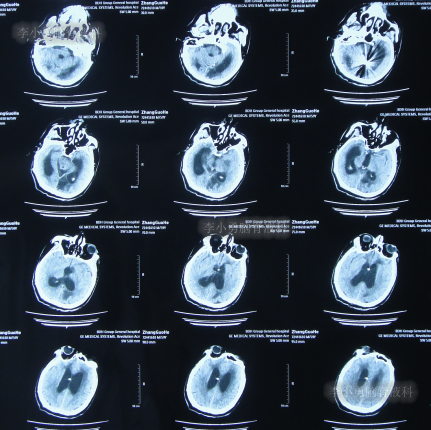

患者于2022年3月16日早晨起床后,无诱因突发头痛,恶心及呕吐,嗜睡,急就诊于当地黑龙江省海伦市某医院,查头颅CT扫描脑出血(片子丢失),因技术有限,120急救车转至上级的黑龙江省哈尔滨某三甲医院,再次复查头颅CT示出血量无明显增多(片子丢失),当天给予脑室外引流术,脑室外引流术后次日查头颅CT示脑出血脑室引流术后(图-1),医生考虑为动脉瘤出血。

图-1:2022年3月17日头颅CT

2022年3月23日(脑动脉瘤栓塞术后5天),查头颅CT示积血减少(图-3);术后身体恢复良好,能自行下地活动。

图-3:2022年3月23日头颅CT

2022年4月27日(入院治疗3天),脑脊液培养出细菌,给予抗感染治疗,查头颅CT示脑室扩张加重(图-5)。

图-5:2022年4月27日头颅CT

抗感染治疗28天即2022年5月25日,查头颅CT示仍脑积水(图-6),脑脊液仍有细菌。

图-6:2022年5月25日头颅CT

抗感染治疗41天即2022年6月7日,脑脊液化验细菌消失,但查头颅CT示仍脑积水(图-7)。

图-7:2022年6月7日头颅CT

2022年6月13日(脑室腹腔分流术后5天),术后患者仍走路不稳,有时胡言乱语,言语不清,小便失禁,查头颅CT(图-8)示脑室仍有扩张。

图-8:2022年6月13日头颅CT

2022年6月17日(分流术后9天即第2次该院治疗53天),查头颅CT虽仍有脑积水(图-9),但仍让患者出院,出院时:仍走路不稳,有时胡言乱语,言语不清,小便失禁;转至当地的某医院进行治疗。

图-9:2022年6月17日头颅CT

在当地的某医院进行康复治疗1个月的时间,患者症状无改善,期间3次查头颅CT(图-10、图-11、图-12)均示仍脑积水。

图-10:2022年6月20日头颅CT

图-11:2022年7月1日头颅CT

图-12:2022年7月12日头颅CT

入院时查头颅CT示脑室分流术后仍脑积水(图-14)。

图-14:2022年7月22日头颅CT

图-15:术后头颅CT

2022年9月13日(住院治疗53天),常规查头颅CT示脑室引流术状态(图-22)。

图-22:2022年9月13日头颅CT

2022年10月11日(住院治疗80天),进行了脑室腹腔分流术。脑室腹腔分流术次日查头颅CT和身体均无异常(图-23)。

图-23:2022年10月12日头颅CT

2022年12月9日(李小勇脑脊液科治疗4月余)出院,出院时:身体一切正常(图-24),头颅CT未见异常(图-25)。

图-25:出院时头颅CT